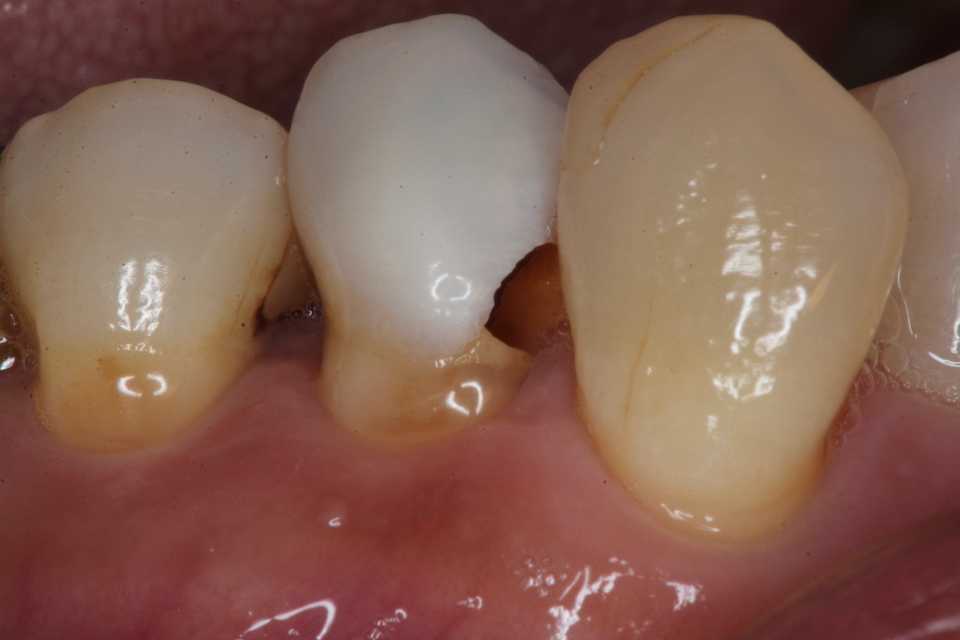

50代女性、左上5-7ブリッジ脱離、7番2次カリエス+Per(根尖性歯周炎)、強度の外傷性咬合この方、ひどい食いしばりで歯が壊れてしまう。噛み合わせの左下7番も歯冠が崩壊しつつある。7番はブリッジが脱離していて、内部は虫歯でドロドロ。Perつまり根管充填が緊密ではなく、歯根内部は細菌だらけで根の周りにはひどい炎症がある。まずはレントゲン写真から。7番の歯根の周りが炎症で黒くなっているのが分かると思う。ブリッジを全部外すと咬合が狂うので、とりあえず7番だけカットして内部を見てみた。根管充填材が見えるところまで軟化象牙質を除去して、3MIX+α-TCPを入れて根管内部を殺菌することにした。根管充填材の周りは黒くなっているのが見えると思うが、これは硫酸塩還元細菌の代謝産物の硫化鉄:FeSで、理想に反して根管充填材はゆるゆるの緊密充填ではないことを示している。このような状況は普通のことだ。歯根内部は細菌だらけということだが、ゆるゆるだから根管充填材を全部除去する必要もない。ゆるゆるの隙間から3MIX(抗菌剤)は浸透し根管は殺菌される。外傷力を弱めるために咬合調整を繰り返している。コア部分は隙間に細菌由来の黒色物質FeSがこびりつき、真っ黒。ポンティック下も細菌のコロニーでドロドロ歯質は残っているように見えるかもしれないが、ボンディング材が効く程度に軟化象牙質(虫歯)を除去すると、残根状態になる。つまり通常治療では抜歯しかないということだ。しかもPerでグラグラの動揺度2〜3、垂直性同様有りだ。とてもこのままではブリッジの支台には使えそうもない。ピンク色の根管充填材が見えると思うが、周りは真っ黒だ。その真っ黒になった隙間から細菌は侵入するし、3MIXも浸透する。こうではない緊密な根管充填治療は垂直加圧法でしか見られない。3MIX+α-TCPCR(ダイレクトボンディング)で覆う。これでないと微小漏洩が起こり失敗する。丸い形はラウンデッド・コアと呼び、この形が咬合力を内向きに集中させ歯根を守る。ポストは歯根の外側にこじるような応力を生じるので歯根を壊してしまいやすい。補綴物が必要な時はピンレッジで維持力を得る。これはCAD/CAMでは作れないだろう。これで2〜3週間様子をみる。外傷性咬合のコントロール(ナイトガードや行動療法)をしながら。つづく